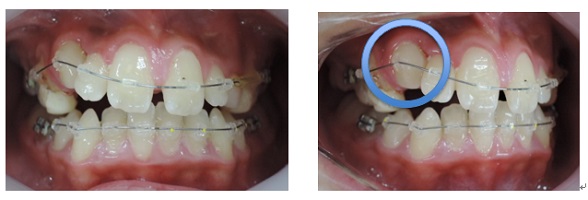

出来るだけ見えにくい矯正装置(ブラケット)を上下顎に装着して歯並びを整えていきます。矯正装置を装着後3日から7日ぐらいまでの間は歯が動きだすために軽い痛みを感じることがあります。

次にMEAW(マルチループ)を利用する事で咬み合わせの高さや前歯の傾斜を整えていきます。

また、MEAW(マルチループ)はゴムを24時間使用する事で最大の効果を発揮することが出来ます。

当院では簡易なMEAW(マルチループ)を使用する事で上下の前歯部をより綺麗な歯並びにしていきます。

この時にも24時間使用するゴムが大切です。

○印の中にある突起は永久歯の犬歯です。